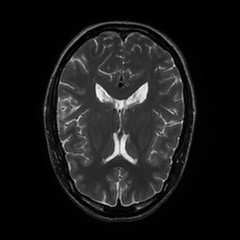

Limited by imaging systems, the reconstruction of Magnetic Resonance Imaging (MRI) images from partial measurement is essential to medical imaging research. Benefiting from the diverse and complementary information of multi-contrast MR images in different imaging modalities, multi-contrast Super-Resolution (SR) reconstruction is promising to yield SR images with higher quality. In the medical scenario, to fully visualize the lesion, radiologists are accustomed to zooming the MR images at arbitrary scales rather than using a fixed scale, as used by most MRI SR methods. In addition, existing multi-contrast MRI SR methods often require a fixed resolution for the reference image, which makes acquiring reference images difficult and imposes limitations on arbitrary scale SR tasks. To address these issues, we proposed an implicit neural representations based dual-arbitrary multi-contrast MRI super-resolution method, called Dual-ArbNet. First, we decouple the resolution of the target and reference images by a feature encoder, enabling the network to input target and reference images at arbitrary scales. Then, an implicit fusion decoder fuses the multi-contrast features and uses an Implicit Decoding Function~(IDF) to obtain the final MRI SR results. Furthermore, we introduce a curriculum learning strategy to train our network, which improves the generalization and performance of our Dual-ArbNet. Extensive experiments in two public MRI datasets demonstrate that our method outperforms state-of-the-art approaches under different scale factors and has great potential in clinical practice.